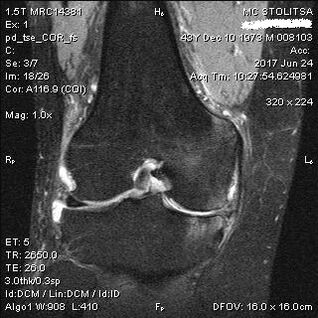

El diagnóstico de artrosis de la articulación de la rodilla se realiza en el consultorio de un reumatólogo u ortopedista. El médico examina la articulación afectada, la repara, escucha las quejas y hace preguntas adicionales. Realice algunas pruebas, por ejemplo, pidiéndole al paciente que doble la pierna o que camine unos pasos. Luego, si es necesario aclarar el alcance de la enfermedad o la naturaleza de los cambios patológicos, lo derivará a estudios adicionales. Por ejemplo, para tomografía computarizada o radiografía.